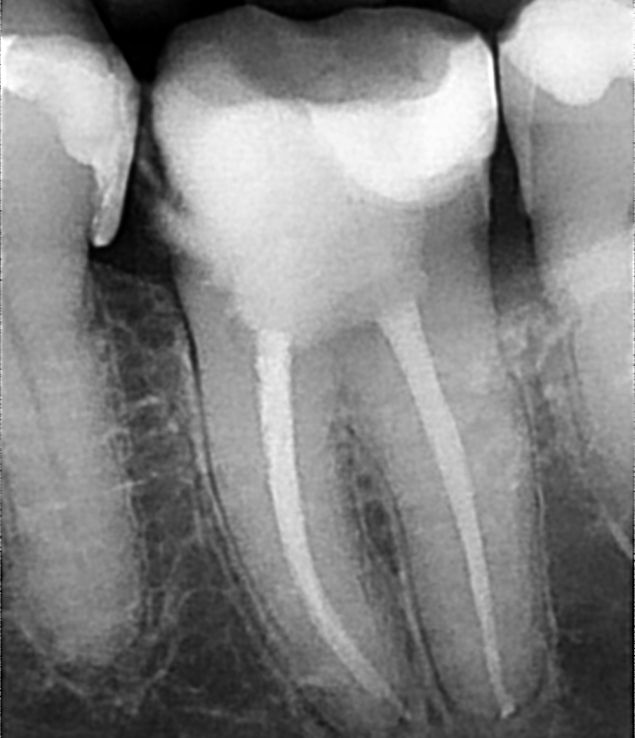

Endodoncija